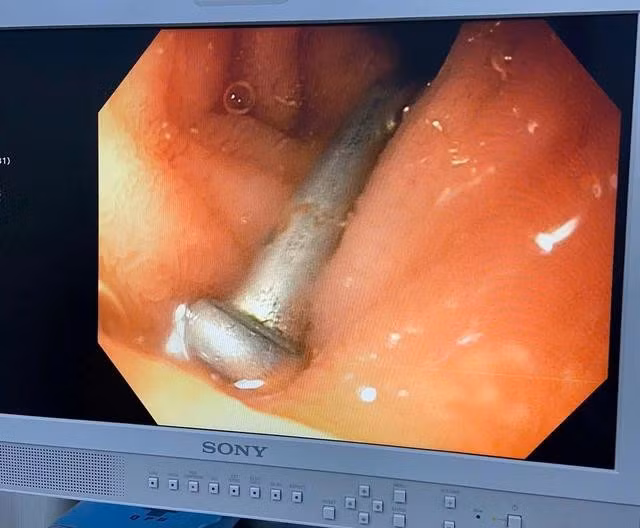

Để gắp dị vật nói trên, các bác sĩ dùng phương pháp nội soi đường tiêu hóa, gắp ra dị vật trong tá tràng bé trai. Dị vật được xác định là 1 cây đinh sắt dài 3 cm.

Chiều 30.3,Bệnh viện Sản - Nhi tỉnh Quảng Ngãi cho biết, sau khi được gắp lấy ra cây đinh sắt dài 3 cm ở tá tràng, bé trai 6 tuổi ở H.Minh Long (Quảng Ngãi) đã ổn định sức khỏe.